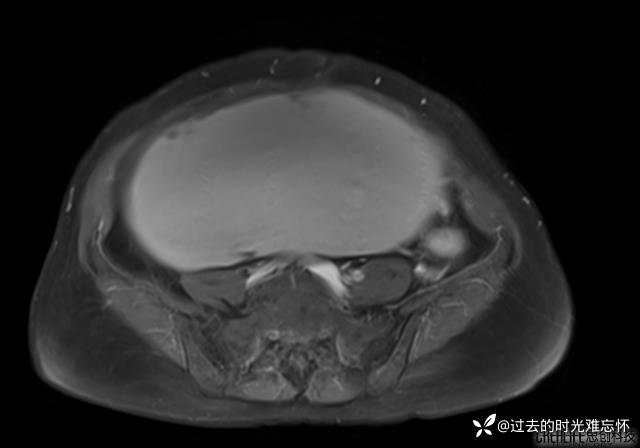

患者性别:女

患者年龄:65岁

主诉: 发现腹部隆起半年余。无其他明显不适。

浆液性囊腺瘤 (22)